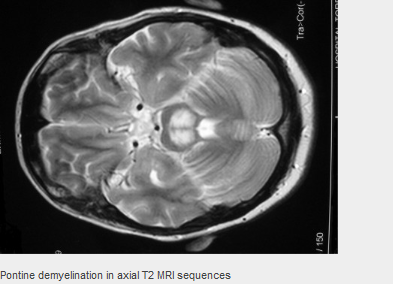

Severe cases require to raise plasma sodium concentration to avoid pontine and extra-pontine myelinolysis

What is a serious complication of SIADH?

Central pontine myelinolysis (CPM or osmotic demyelination syndrome) - Occurs in people with longstanding SIADH who undergo overaggressive treatment of hyponatraemia. CPM is characterised by demyelination of pontine, basal ganglion, and cerebellar regions.